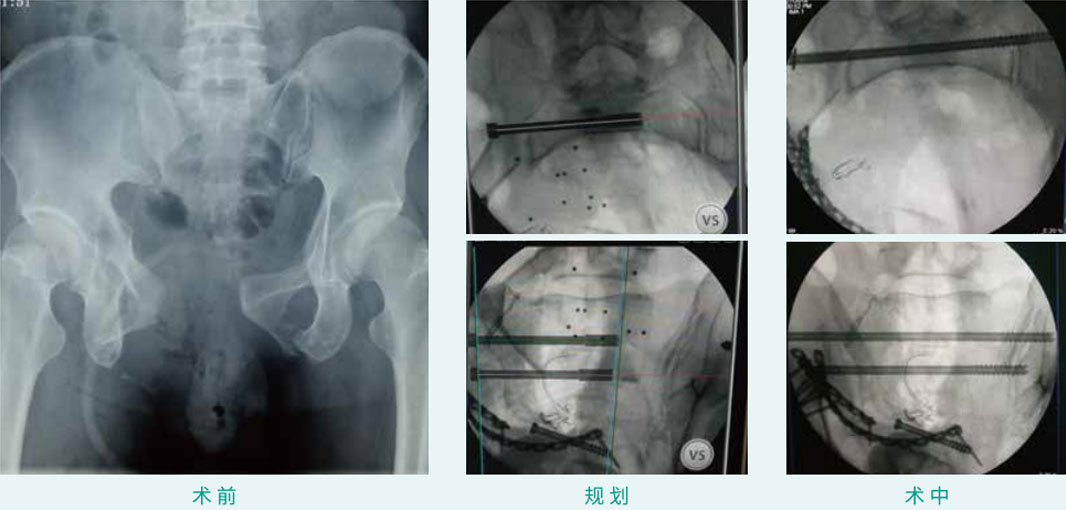

经皮空心螺钉内牢靠术

天玑? 辅助骶髂螺钉(骶1、骶2)经皮空心螺钉内牢靠术

基本情形:患者男 , ,27岁 , ,骨盆骨折

机械人累积用时:15分钟

植入物:2枚空心螺钉

病例泉源:中国人民解放军总医院(301医院) 陈华